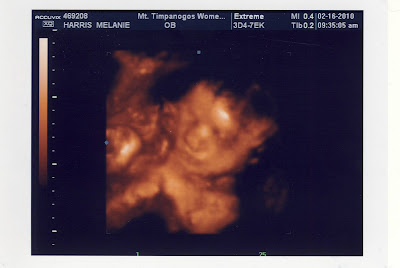

We had a 3D ultrasound done this last week when Lynn and Eileen and Summer were in town. We think our little girl is pretty darn cute already! It just makes us want to see her now!

She stuck out her tongue!